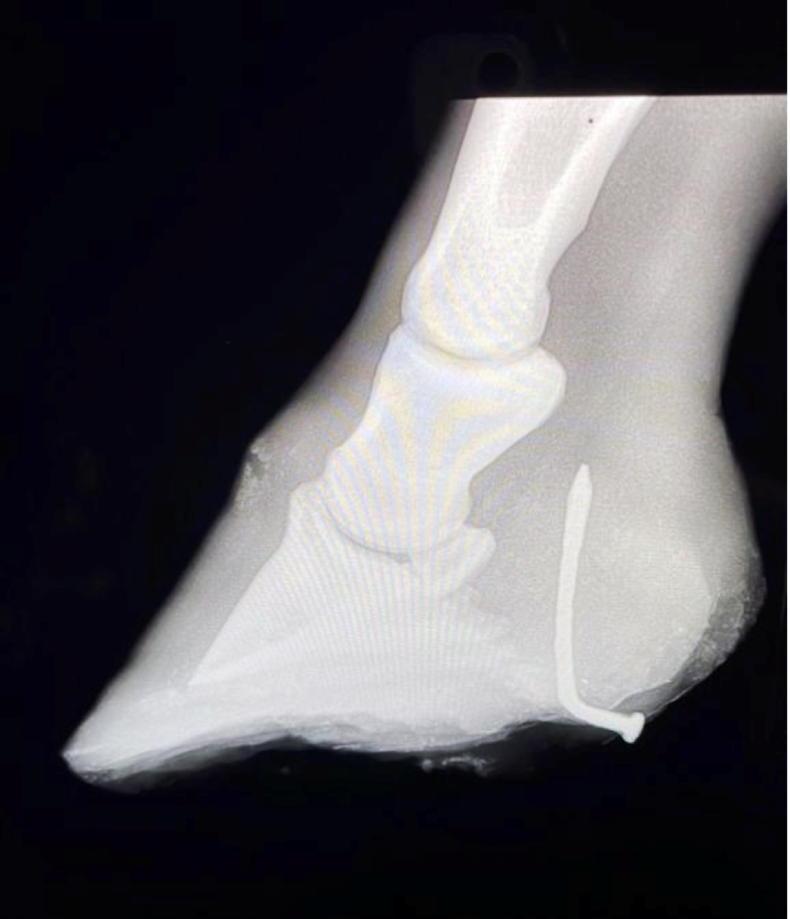

Where possible, leave the nail in place until a veterinary examination can take place. A foot X-ray with the nail in situ will quickly reveal its direction of travel, and help figure out the most appropriate course of treatment. Ideally, keep the horse from moving around and causing further damage while waiting for assistance. Clean, dry footing will help keep the wound from getting further dirt packed into it. Two rolls of bandage, or a thick piece of aeroboard with a hole cut in it, can be placed over the sole either side of the injury site and taped or bandaged in place to help prevent the horse driving the object further into its foot.

Figure 3 is a photo of a nail that was found to have pierced the base of a horse’s frog, close to the heel bulbs. The angle of entry on closer inspection looked very ominous, with the direction of travel appearing to be towards the navicular bone. The X-ray (figure 4) revealed however, that this horse had been lucky and the nail had bent away from the bone and was instead stuck in the heel bulbs – painful no doubt, but not life-threatening. The nail was removed and the tract in the hoof cleaned and flushed. The foot was dressed and bandaged and a course of antibiotic therapy, a tetanus booster, and pain relief happily resulted in a full recovery for this horse.